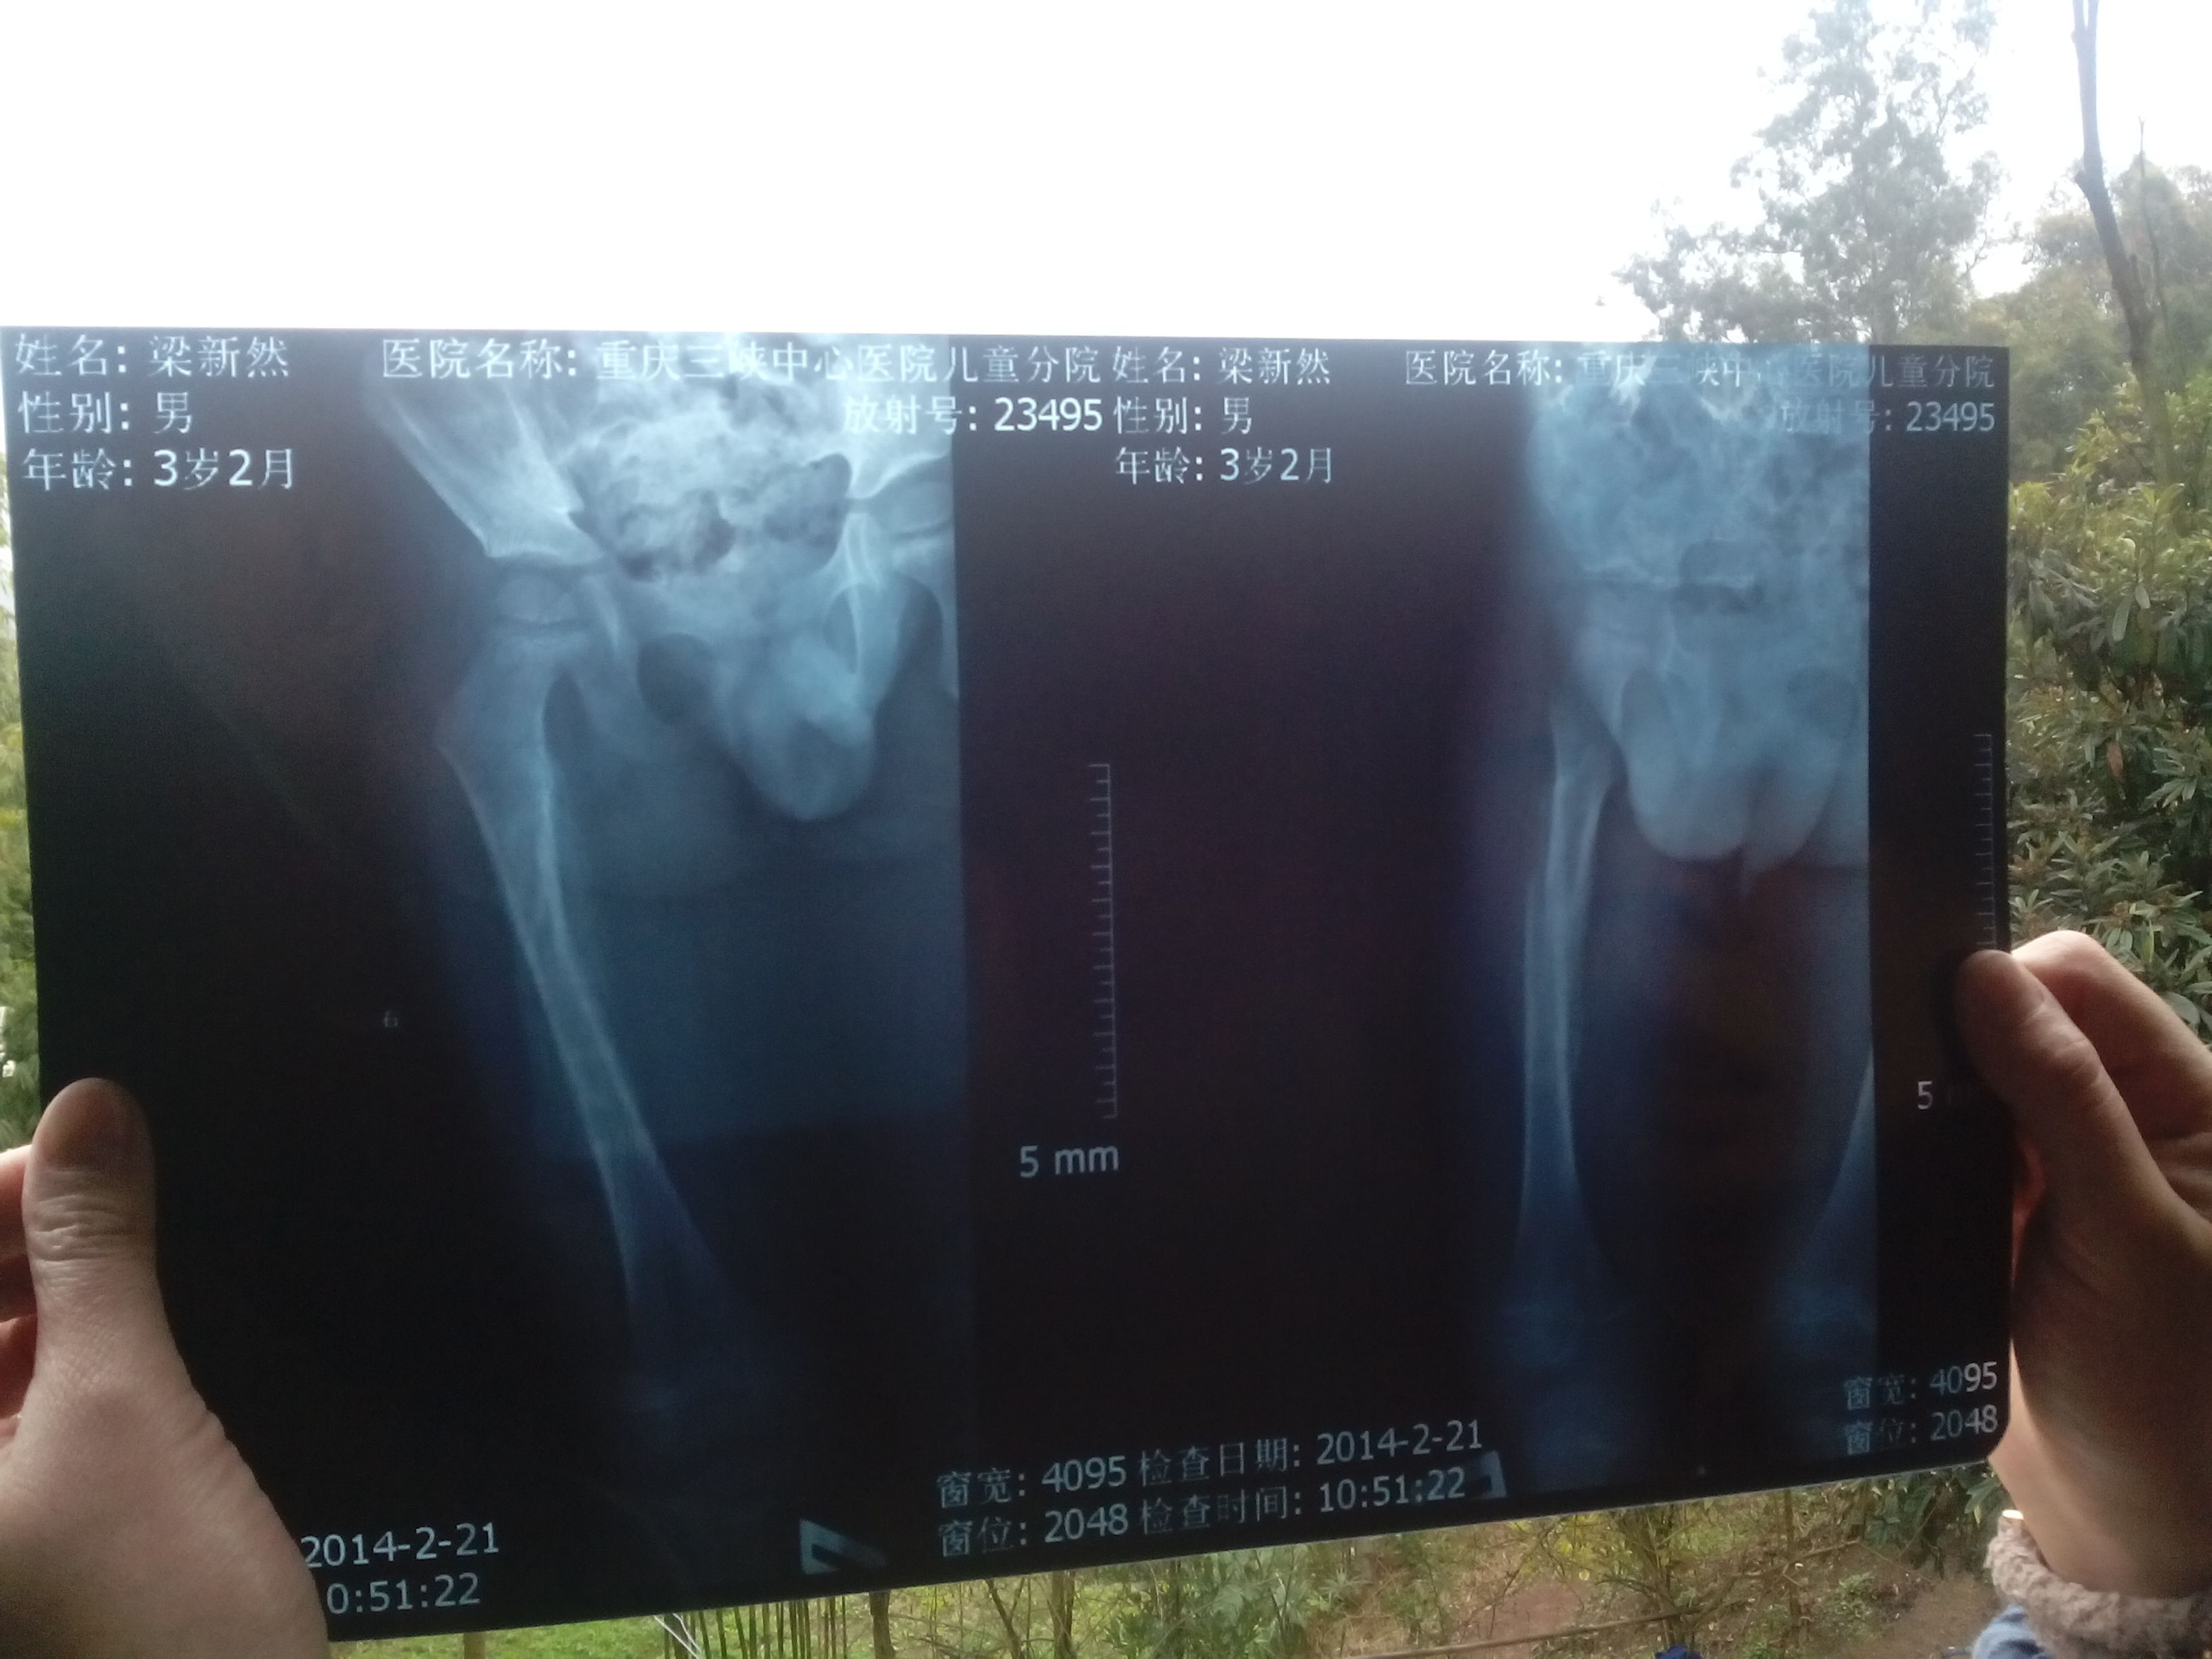

以下是一个3岁小孩右腿股骨骨折后,做牵引23天拍的片(2014年1月28号骨折,2014年2月23

病情分析: 你好!通过片子看孩子的股骨的上段有骨折的情况,侧位片见骨质断端有移位的情况,骨折还没有愈合。 指导意见: 给予取下内固定是错位的,会造成骨折的继续移位的,去医院给予拍片子复查,给予相应的处理。